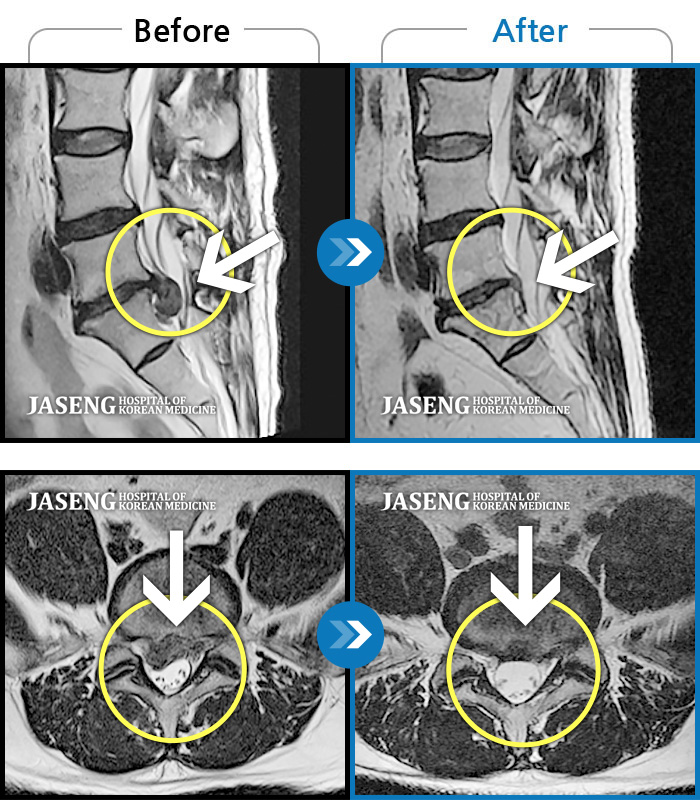

허리디스크

일산 · 김태용 원장

허리와 좌측 하지 방사통이 심하시어 보행이 거의 힘들었다.

촬영시기

2021.03.06 ~ 2021.07.15

2021.07.23

조회수 502